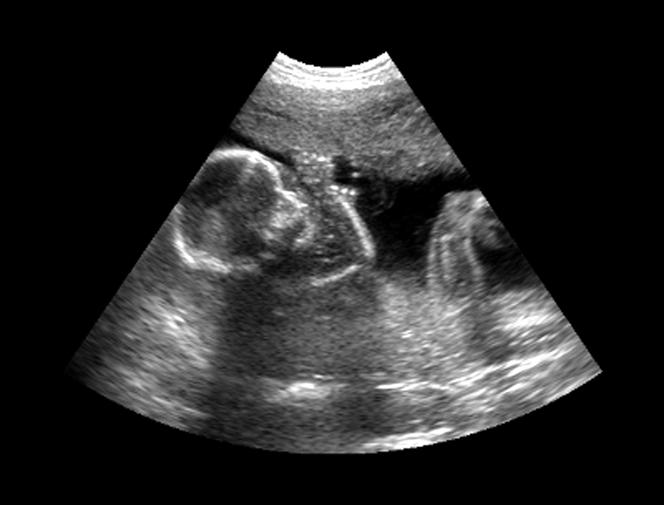

J’ai donc travaillé sur la coordination bimanuelle, sur la façon dont une main joue un rôle de support quand l’autre, généralement la droite, est plus active. J’ai fini par m’intéresser à la latéralité tout court. La stratégie à l’époque était d’observer l’enfant après la naissance, mais si on voulait remonter à l’origine, il fallait pouvoir l’étudier in utero.